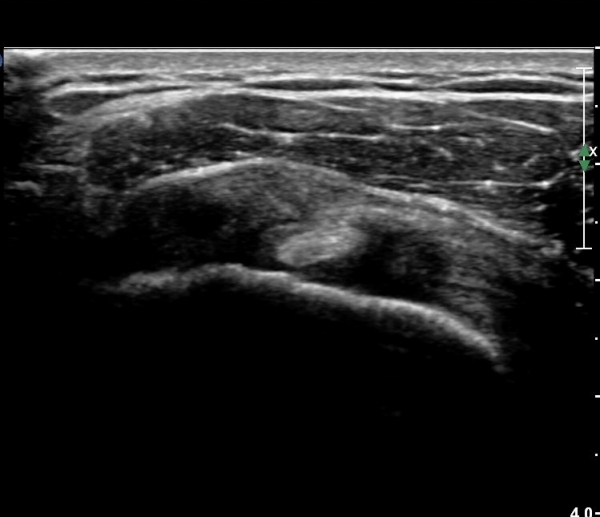

ȸÀü±Ù°³°£°Ý(rotator cuff interval) Ⱦ´Ü¸é°Ë»ç¿¡¼­ °ß°©ÇϱٰǻóºÎ¿Í ±Ø»ó°Ç ³»ÃøºÎ¿¡

ƯÀÌ ¼Ò°ßÀ» º¸ÀÌÁö ¾Ê´Â´Ù(»çÁø 1, 2).